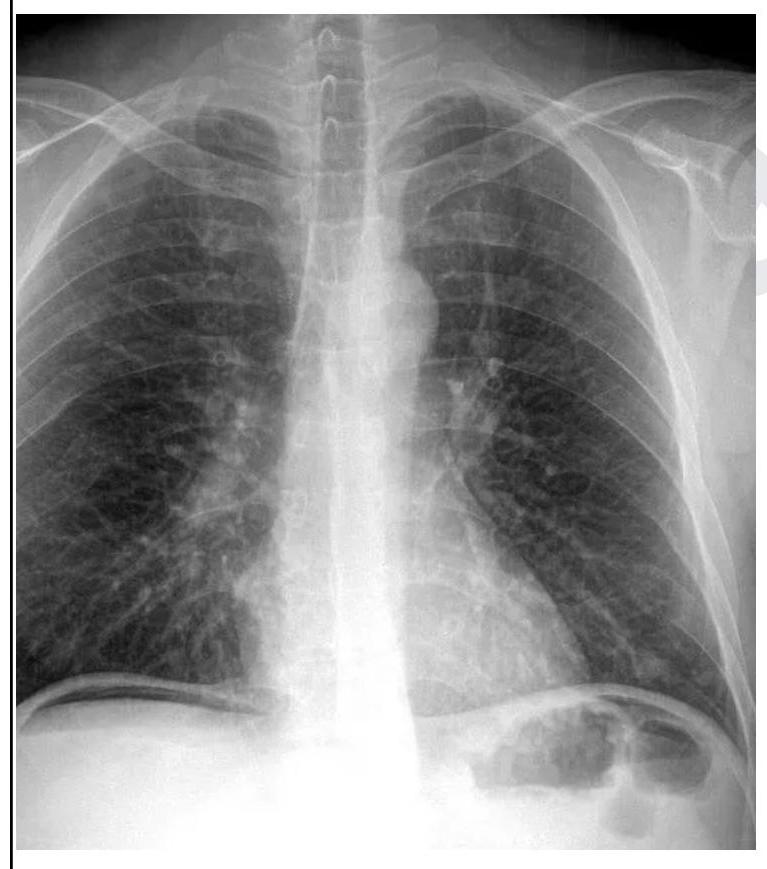

A 26 year old male patient was brought to the emergency department with abdominal pain and obstipation for 3 days. He gives a history of bull gore to the abdomen 3 days back. His chest X-ray is given below. What is the probable diagnosis?

Explanation: ***Hollow viscus perforation*** - The chest X-ray clearly shows **free air under the diaphragm** (pneumoperitoneum), which is a hallmark sign of a perforated hollow viscus in the abdomen. - The history of **bull gore to the abdomen** and subsequent abdominal pain and obstipation further supports a traumatic perforation of a stomach or intestinal segment. *Hemothorax* - Hemothorax would present as **fluid in the pleural space**, typically seen as blunting of the costophrenic angles or an effusion on X-ray, which is not evident here. - While trauma can cause hemothorax, the prominent finding on this X-ray is intra-abdominal air, not intrathoracic fluid. *Pneumothorax* - Pneumothorax is characterized by the presence of **air in the pleural space**, leading to lung collapse and absence of lung markings in the affected area, which is not observed on this X-ray. - The air seen is clearly **below the diaphragm**, indicating intra-abdominal free air, not air in the chest cavity surrounding the lung. *Intestinal obstruction* - Intestinal obstruction typically presents with **dilated bowel loops** and **air-fluid levels** on an abdominal X-ray, along with abdominal pain and obstipation. - While the patient has obstipation, the primary X-ray finding is free air under the diaphragm, which is not characteristic of an uncomplicated intestinal obstruction.